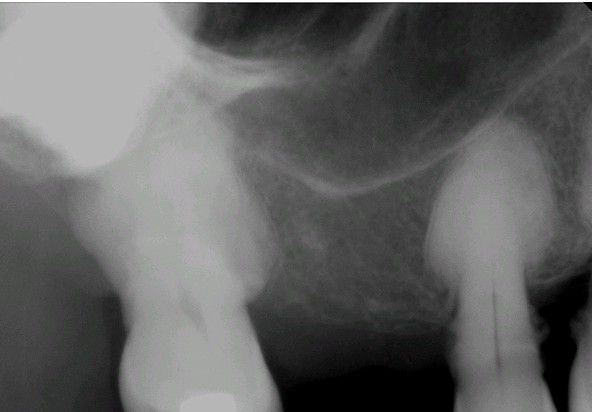

Hypercementosis

Periapical radiograph of the tooth. Note the radiopaque enlargement of the apical portion of the tooth.